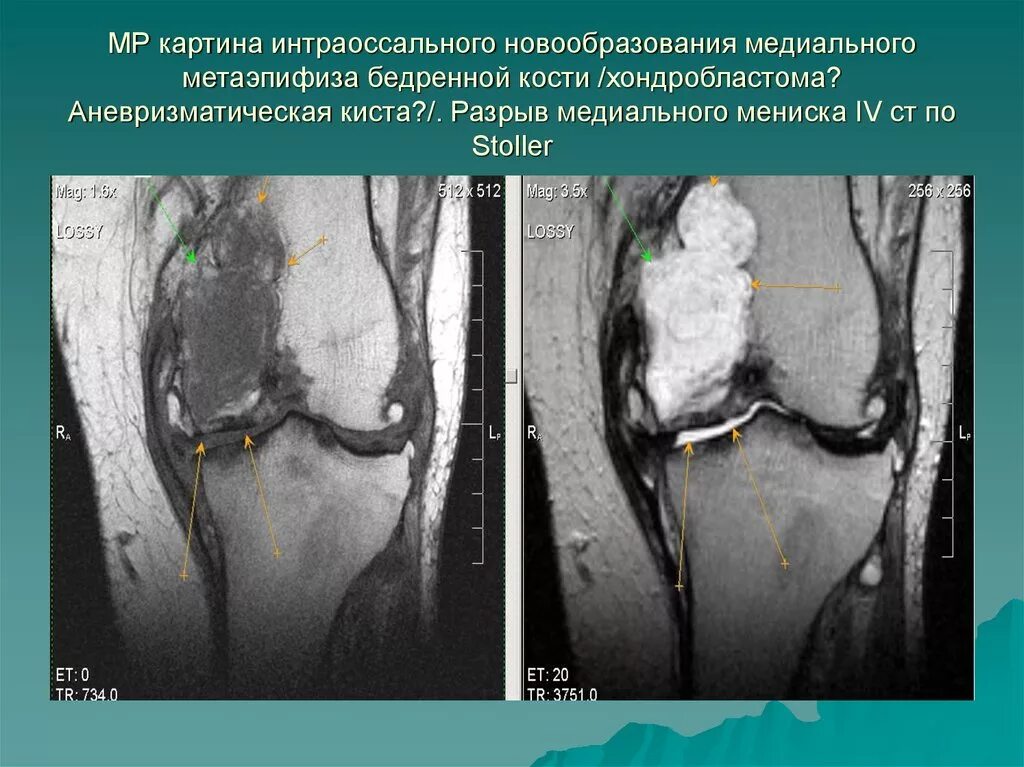

Мр картина дегенеративных изменений медиального мениска